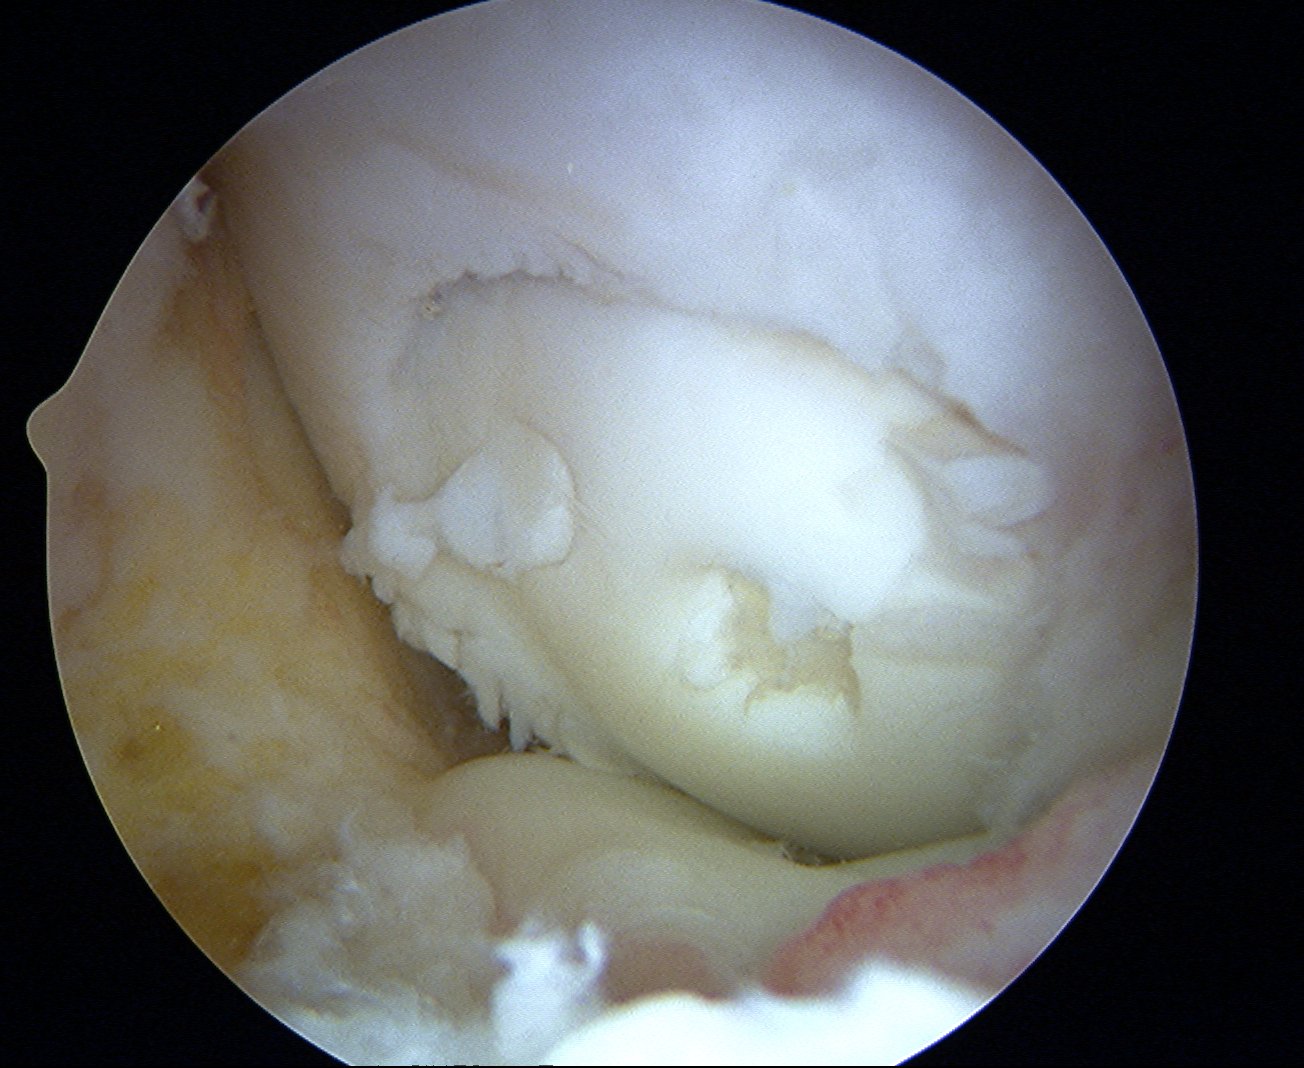

Repeat

Technique Mosaicplasty Type 3 OCD